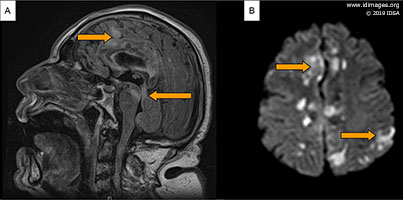

- The patient was admitted to the hospital and was scheduled for a Magnetic Resonance Imaging (MRI) of the brain. On day 2 his neurological status rapidly deteriorated. He became acutely confused and obtunded requiring intubation for airway protection and transfer to the medical intensive care unit. His temperature increased to 100.4°F (38.0°C) and he was empirically started on vancomycin, meropenem and acyclovir. Infectious diseases service was consulted. Brain MRI showed diffusion restriction and corresponding high T2 and FLAIR signal involving the tectum and midline periaqueductal region of the midbrain and a small area of the medial superior left cerebral hemisphere; there was midbrain edema with associated stenosis of the aqueduct and obstructive hydrocephalus of the third and lateral ventricles (Figure 3A and B).

- Figure 3: MRI brain without contrast on day 3. (A) Sagittal FLAIR images showing area of hyperintensity in the tectum and midline pre-aqueductal region of the midbrain. Associated stenosis of the aqueduct with obstructive hydrocephalus. (B) Diffusion-weighted imaging showing high-signal areas in a small area of the medial superior left cerebral hemisphere. There was no definite corresponding apparent diffusion coefficient changes.